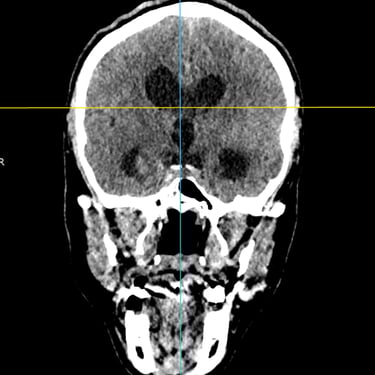

Hidrocefalia Posthemoventricular: Tratamiento con Derivación Ventriculoperitoneal

La hidrocefalia posthemoventricular se produce por alteración en la circulación y absorción del líquido cefalorraquídeo tras una hemorragia intraventricular, generando dilatación ventricular y deterioro neurológico progresivo. Cuando el manejo médico resulta insuficiente, la derivación ventriculoperitoneal constituye el tratamiento quirúrgico de elección. Este procedimiento permite drenar el exceso de líquido cefalorraquídeo desde los ventrículos cerebrales hacia la cavidad peritoneal, reduciendo la presión intracraneal y mejorando los síntomas neurológicos. La intervención oportuna contribuye a estabilizar la función cerebral y a optimizar el pronóstico funcional del paciente.